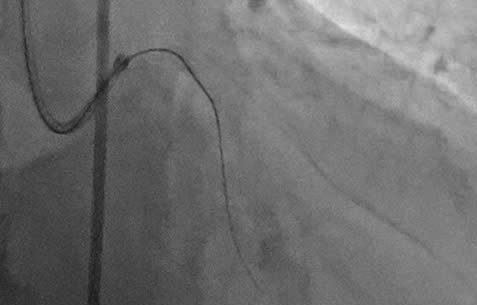

Tổn thương trước chụp động mạch vành

Đưa dây dẫn siêu cứng qua tổn thương động mạch mũ